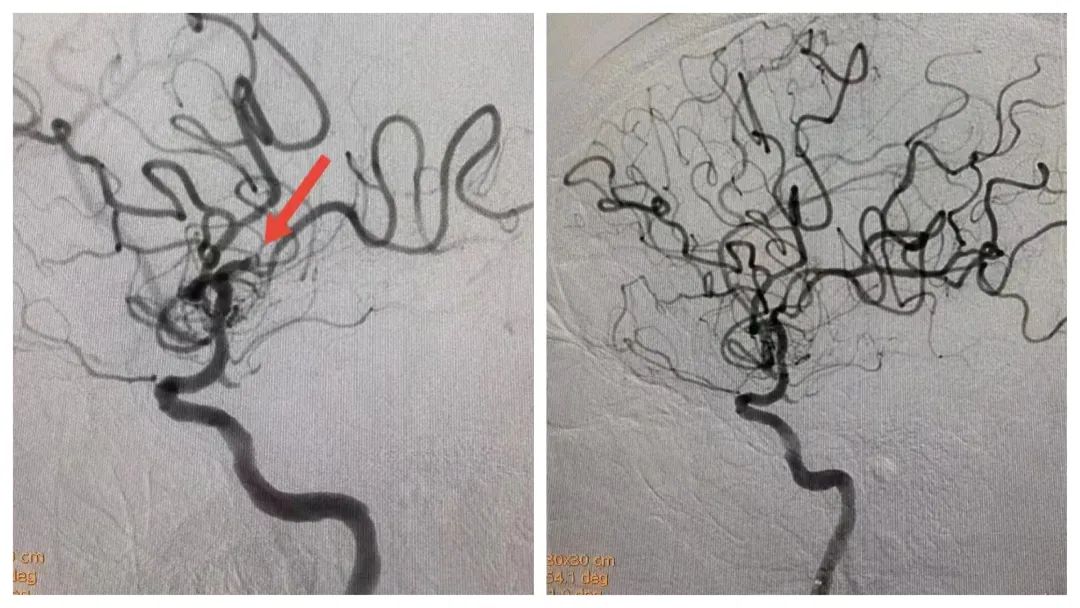

卒中中心李伟旺主任团队接力手术,行脑血管造影,发现张叔左侧大脑中动脉完全闭塞。脑血管造影+支架植入+机械取栓+球囊扩张术,2 个小时,张叔脑血管成功疏通。